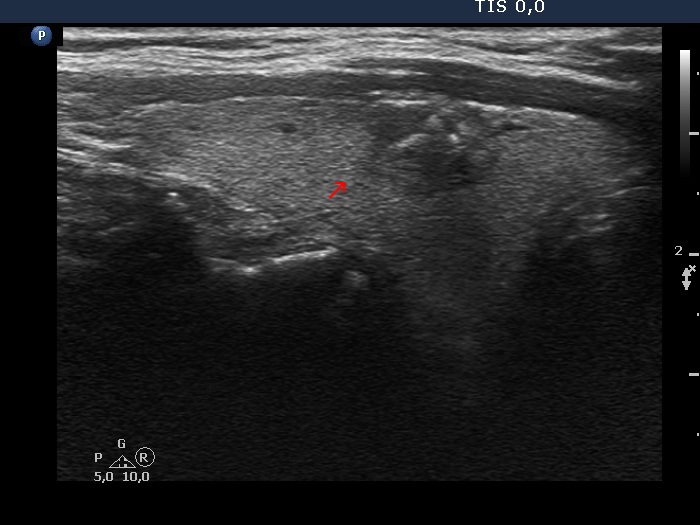

The borders of the nodule - case 2050 (ultrasonographic picture 2b)

Right lobe, longitudinal scan

Right lobe, longitudinal scan. The red arrow points to a spiculation which is characterized by sharp angles.